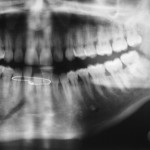

Classification by anatomic region

• Symphysis – Fracture in the region of the central incisors that runs from the alveolar process through the inferior border of the mandible

• Parasymphyseal – Fractures occurring within the boundaries of vertical lines distal to the canine teeth

• Body – From the distal symphysis to a line coinciding with the alveolar border of the masseter muscle (usually including the third molar)

• Angle – Triangular region bounded by the anterior border of the masseter muscle to the posterosuperior attachment of the masseter muscle (usually distal to the third molar)

• Ramus – Bounded by the superior aspect of the angle to two lines forming an apex at the sigmoid notch

• Condylar process – Area of the condylar process superior to the ramus region

• Coronoid process – Includes the coronoid process of the mandible superior to the ramus region

• Alveolar process – Region that normally contains teeth